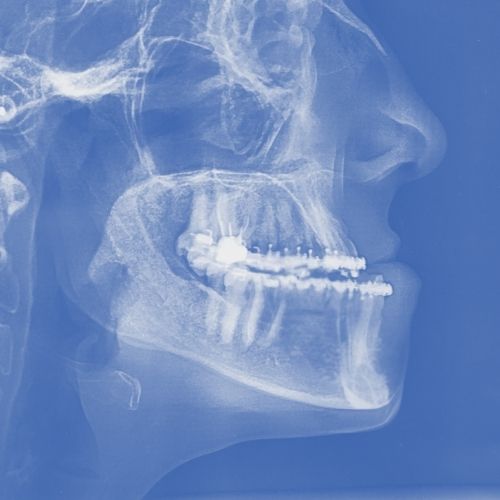

Es una cirugía que recoloca los maxilares superior, inferior o ambos, para corregir maloclusiones y alteraciones del crecimiento facial que no pueden tratarse solo con ortodoncia.

Puede tratarse de una cirugía ortognática bimaxilar, cuando es necesario intervenir ambos huesos, o solo uno, en función del diagnóstico.

Requiere una planificación mas avanzada, con modelos y radiografías en 3D digitalizadas, para diseñar las férulas quirúrgicas que guían al cirujano durante la intervención para un posicionamiento preciso de los maxilares.